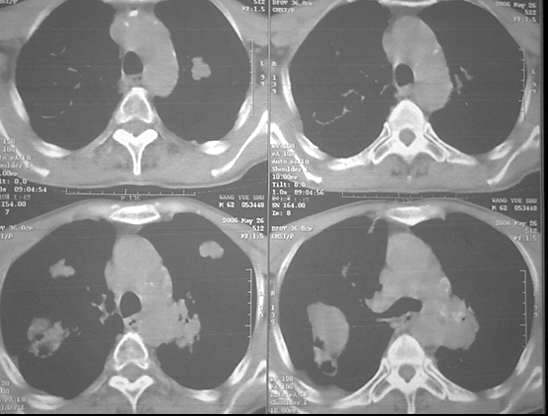

男62肺癌治疗后复查

具体治疗措施不清楚,治疗前空洞很少,请讨论空洞的性质

双肺内及胸壁旁见有多发软组织实性阴影和空洞,实性病变多见有脐凹切迹,贴近胸膜的见有胸膜凹陷征;空洞的壁多为厚薄不均,形态不规则,纵隔内见有较多肿大淋巴结,诊断为双肺内转移性病变。

双肺内及胸壁旁见有多发软组织实性阴影和空洞,实性病变多见有脐凹切迹,贴近胸膜的见有胸膜凹陷征;空洞的壁多为厚薄不均,形态不规则,纵隔内见有较多肿大淋巴结,诊断为双肺内转移性病变。[气囊或孔洞实为腺癌缘肺泡壁生长所致]

右肺门软组织块影,右主支气管及中间段支气管管壁明显增厚,两肺内多发结节及大小不等的类圆形薄壁空洞,纵隔内多发肿大的淋巴结;

考虑:1.右中央型肺癌伴两肺广泛性转移及纵隔转移。

2.多发性空洞需和霉菌性空洞鉴别。